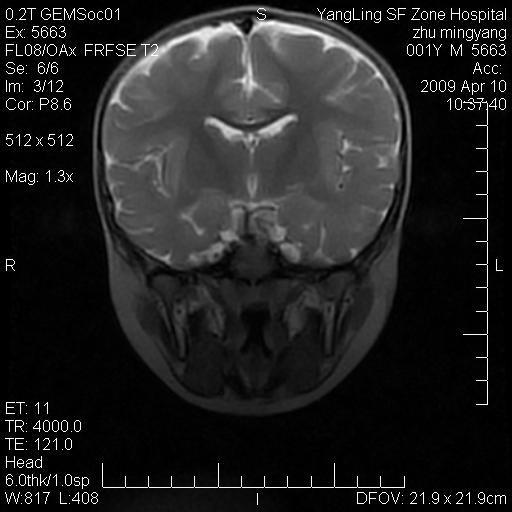

患者:1岁半,两天前外伤收住我院,ct检查小脑占位

考虑星形细胞瘤,建议增强

髓母细胞瘤或血管母细胞瘤,增强后可以鉴别;影像资料见 <。鱼博浪老师的《中枢神经系统ct与mr鉴别诊断》 小脑部肿瘤章节。

髓母细胞瘤或血管母细胞瘤!支持!

支持考虑髓母细胞瘤

考虑----髓母细胞瘤可能性大

考虑髓母细胞瘤或室管膜瘤。

支持髓母细胞瘤。

考虑髓母细胞瘤。

考虑髓母细胞瘤或星形细胞瘤

考虑髓母细胞瘤.

考虑髓母细胞瘤可能性大。

小脑肿瘤.考虑髓母细胞瘤可能.

就病灶部位及临床资料首先考虑髓母.